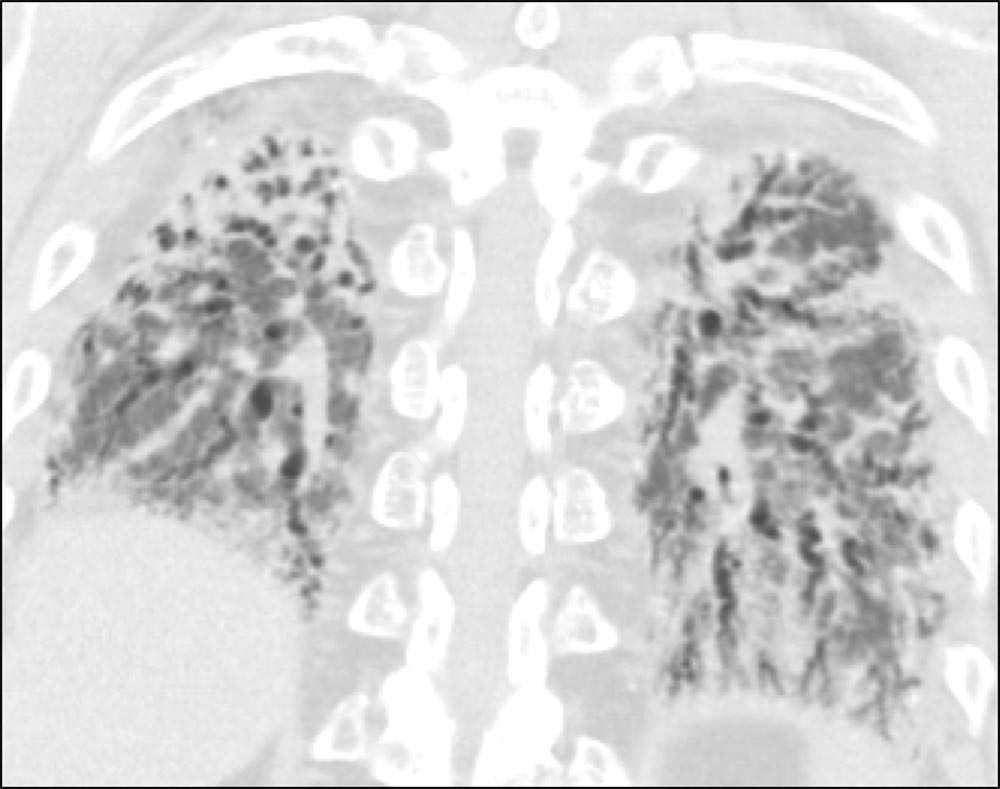

Axial HRCT showing subpleural honeycombing at the bases of the lung in a patient with IPF. On HRCT, honeycomb cysts appear as enlarged airspaces that are often irregular in size, share thick walls, and are stacked upon one another.1 The cysts are typically 3-10 mm in diameter but can be as large as 2.5 cm.1,2 Honeycombing results from the deposition of dense collagen fibers that destroy the characteristic alveolar structure,2 and is typically representative of end-stage lung disease.1 Subpleural, peripheral honeycombing with reticulation in the absence of significant ground glass opacity, consolidation, or non-honeycomb cysts is strongly suggestive of usual interstitial pneumonia (UIP).